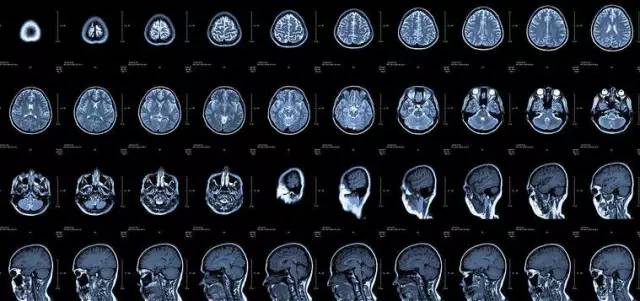

核磁共振:把東西搖搖看

核磁共振機使用較強大的磁場,使人體中所有水分子磁場的磁力線方向一致,這時磁共振機的磁場突然消失,身體中水分子的磁力線方向,突然恢復到原來隨意排列的狀態(tài)。簡單說就相當于用手搖一搖,讓水分子振動起來,再平靜下來,感受一下里面的振動。所以,核磁共振(MRI)也被戲說為是搖搖看的檢查。